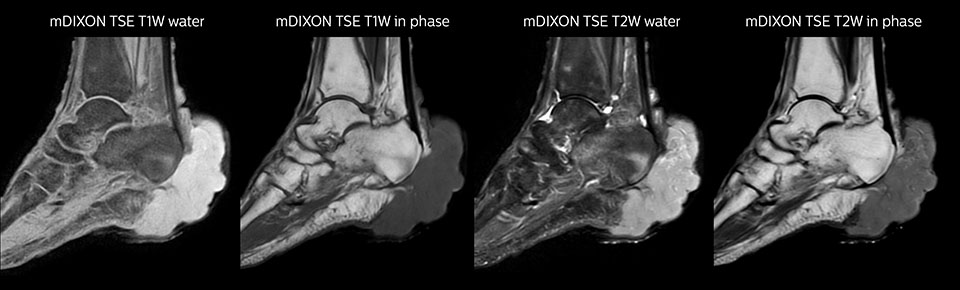

MRI examination on Prodiva 1.5T of a 72-year-old female with a malignant melanoma in the ankle. mDIXON TSE provides excellent fat suppression, without the distortion that is often seen at such extremities.